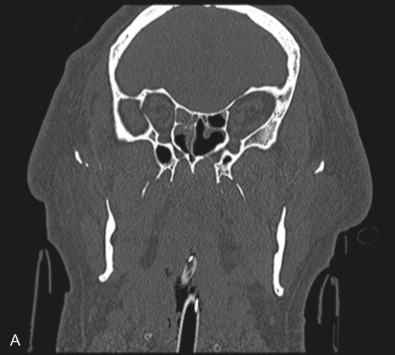

The gold standard for radiographic evaluation is thin-slice helical computed tomography (CT). Midface fractures are confirmed by axial, coronal, and sagittal views. The degree of comminution, bone loss, and detailed images of the fracture patterns can be assessed and juxtaposed to surrounding soft tissue structures. 3D reconstruction, when utilized, can aid in visualizing the complex 3D anatomical orientation of fracture fragments that occur in Le Fort injuries and facilitate reconstructive planning.